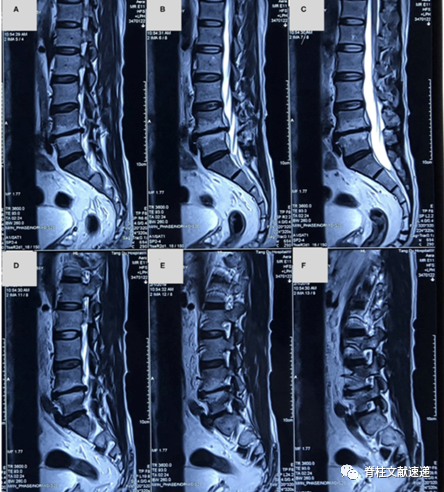

55岁男性,以间断性右下肢放射痛为主诉入院。患者每年都有几次右下肢坐骨神经痛发作,1月前疼痛再次出现,由臀部、大腿后外侧、小腿外侧至足背,休息或姿势改变疼痛症状无改变。无肌力异常、无间歇性跛行,无感觉异常,非甾体类消炎镇痛药和神经营养药治疗无效。MR如下图,L4/5椎间隙变窄,可见椎间盘突出。

入院3天后,查体见患者右侧臀部和右小腿的疱疹样皮损,如下图所示。咨询皮肤科后诊断坐骨神经带状疱疹,给予抗病毒治疗,3天后症状减轻,3月后症状完全缓解。